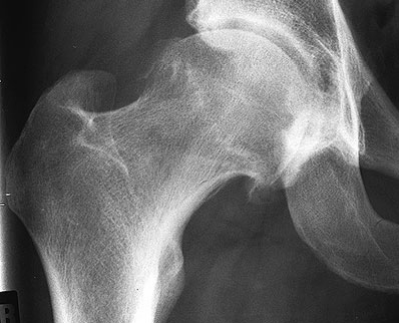

Bei der oben beschriebenen Bewegung im Hüftgelenk stossen in diesem Fall die beiden Knochen zusammen (= impingieren) und führen zu einem chronischen Reizzustand und zu irreparablen Gelenkschädigungen. Im Spätstadium nennt man diese Schädigungen Coxarthrose. Gründe für diesen mechanischen Konflikt können eine Fehlrotation des Schenkelhalses, eine mangelnde Taillierung zum Hüftkopf oder eine zu starke vordere knöcherne Überdachung des Pfannenrandes sein. Anfänglich führt dies bei entsprechender körperlicher Beanspruchung zu einer schmerzhaften Einschränkung der Hüftbeweglichkeit. Mit der Zeit werden diese Veränderungen am Knochen auch im Röntgenbild sichtbar (Abb. 2).